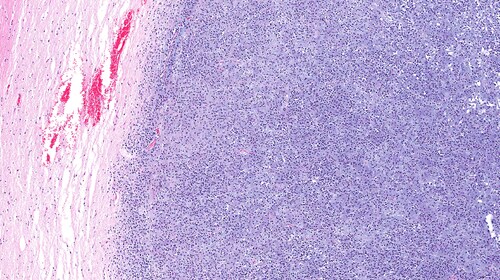

Biobanking comprises more than just tissue sample storage. Biobanks often prepare samples and sample reports to aid future research uses. In Australia, the Royal College of Pathologists of Australasia (RCPA) stipulates reporting protocols. Its recommendations include describing the specimen’s macroscopic features (e.g., size, number and appearance), the proportion of the specimen processed, the histologic type of cancer and the tumor grade (according to the World Health Organization’s 2007 classifications), and immunohistochemical results and ancillary studies. White et al. (2015) assessed the quality of pathology reports for grade III and IV gliomas in Australian biobanks using a checklist derived from reporting protocols of the RCPA and the College of American Pathologists.1 In doing so, they endeavored to facilitate quality improvement across patient management decisions based on pathology reports by ensuring that they contain unambiguous information for clinical decision-making.

White et al. found that 62% (n = 368) of the reports that they included in their analyses were completed by neuropathologists. Of these, 339 were surgical neuropathologists, and the remaining 189 were general pathologists. Their key findings from the nine quality score parameters were as follows: